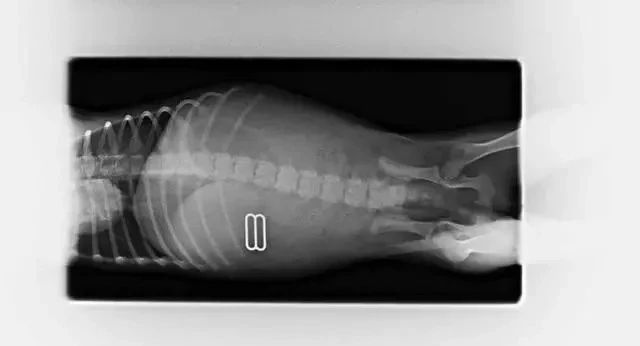

在X光照射下才终于查明病因,狗狗胃中塞满了异物。

医生立即安排了手术,结果让人大吃一惊:竟从狗子的胃里取出了19个安抚奶嘴。主人从来没有注意到安抚奶嘴居然被狗狗偷吃了这么多。